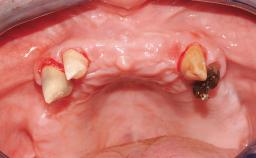

A 56-year-old female patient was referred to the clinic because of retention problems with her mandibular denture. She had been completely edentulous for more than 33 years and wore her sixth set of complete conventional dentures, which had been delivered 5 years previously. An oral surgeon had performed a vestibuloplasty in the interforaminal region of the mandible with a piece of skin tissue 12 years earlier. The panoramic radiograph and lateral cephalometric radiograph exhibited the hypotrophy of the inferior alveolar process. The mandible was a Cawood class VI,and the height of the mandible in the interforaminal zone was 15 mm.